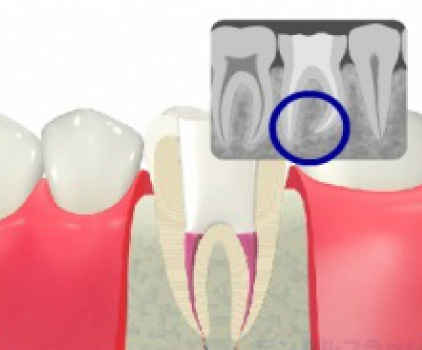

根管治療BEFORE・AFTER

確認のためレントゲンを撮ります。